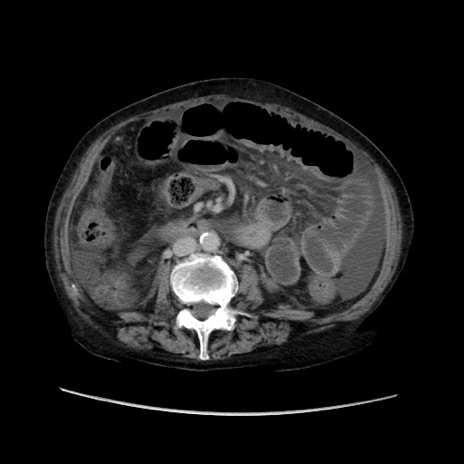

矢状断像